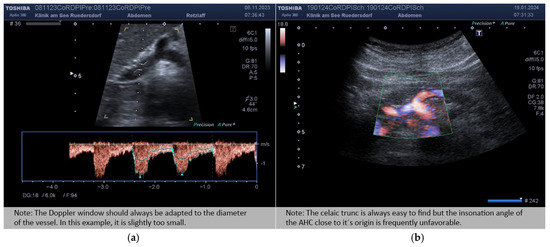

2.3.2. Location of the Probe, Insonation Angle, and Doppler Window